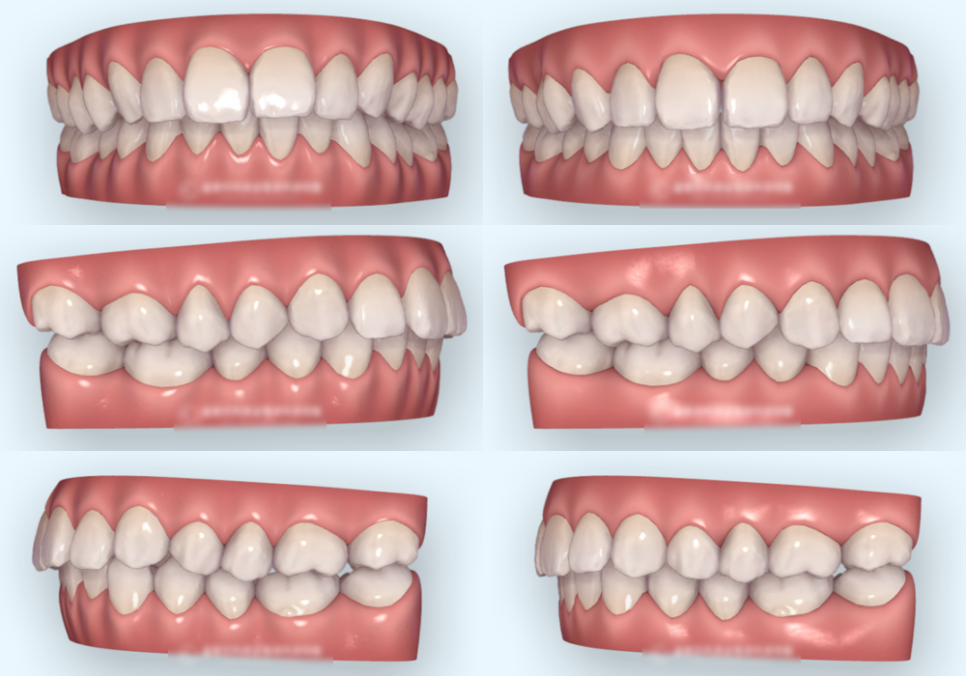

구강 내 모습을 보았을 때

위아래 턱 모두 좁은 악궁을

가지고 있는 것을 확인할 수 있었는데요.

위 앞니가 아래 앞니를

과도하게 덮는 과개교합이 확인되었으며,

아래 앞니의 총생이 있었습니다.

3차원 가상 시뮬레이션으로

치아 이동 경로를 설계하여

가상의 결과를 확인한 뒤 진료 과정을

진행합니다.